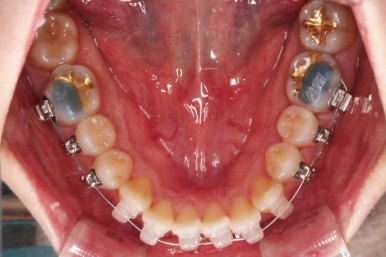

초진 시, 입안의 모습이에요.

결손부위가 눈에 띄고요.

결손부위가 양쪽에 있다보니 윗니 중간에 틈새가 벌어졌네요.

뒤쪽의 빈공간으로 치아들이 도미노처럼 쓰러져서 그렇습니다.

앞니의 약간의 틈새, 약간의 삐뚤어짐, 약간의 중앙선 틀어짐 등 심하진 않으나 약간씩의 문제점들이 있네요.

환자분이 선택하신 장치는 데이몬 클리어라고 하는 자가결찰 세라믹 장치입니다.

자가결찰 세라믹 중에 가장 심미적으로 우수한 장치가 데이몬 클리어인데요.

철사를 제외한 모든 파트가 세라믹으로 되어있습니다.

장치를 부착한 모습 참고해 주시고요.

아랫니는 중앙선을 맞추기 위해서 미니스크류를 이용해 한 쪽으로 당기는 중이고요.

이 과정에서 아랫니들이 약간은 뒤로 들어가져서 아랫입술 부위의 돌출감을 아주 약간은 줄일 수 있습니다.